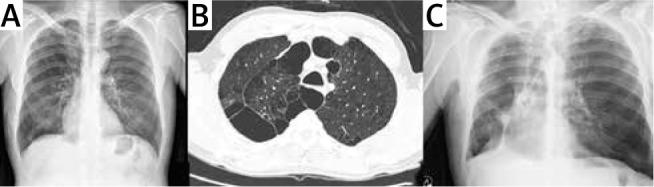

https://cdn.ncbi.nlm.nih.gov/pmc/blobs/02f3/7526494/62dc77987737/KITP-17-41808-g002.jpg

https://cdn.ncbi.nlm.nih.gov/pmc/blobs/02f3/7526494/9311fbc8e641/KITP-17-41808-g001.jpg